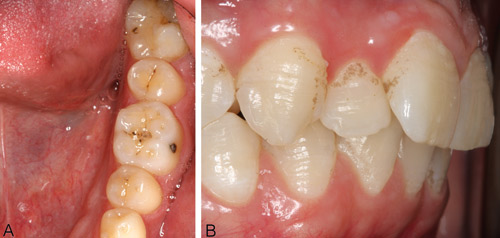

De viktigste og alvorligste komplikasjonene på lang sikt ved kreftbehandling generelt er spyttkjerteldysfunksjon, med xerostomi, trismus, risiko for utvikling av osteoradionekrose og medikamentrelatert osteonekrose, samt dentale og skeletale mineraliserings og/eller utviklingsforstyrrelser ved behandling av barn og unge (figur 1,2). (8).

Figur 1. Dentale utviklingsforstyrrelser hos to voksne kreftoverlevere behandlet med cytostatika for akutt lymfatisk leukemi og som deltar i en pågående tverrfaglig PhD-studie om langtidsfølger av kreftbehandling i barne- og ungdomsalder (Wilberg P, Herlofson BB). A: Mikrodonti av tann 37 (også 47) hos 30 år gammel mann behandlet i 2 - 3 årsalder. B: Mineraliseringsforstyrrelser på flere tenner i form av furer og groper hos 18 år gammel mann behandlet fra 2.5 årsalder over tre perioder (foto Wilberg P).